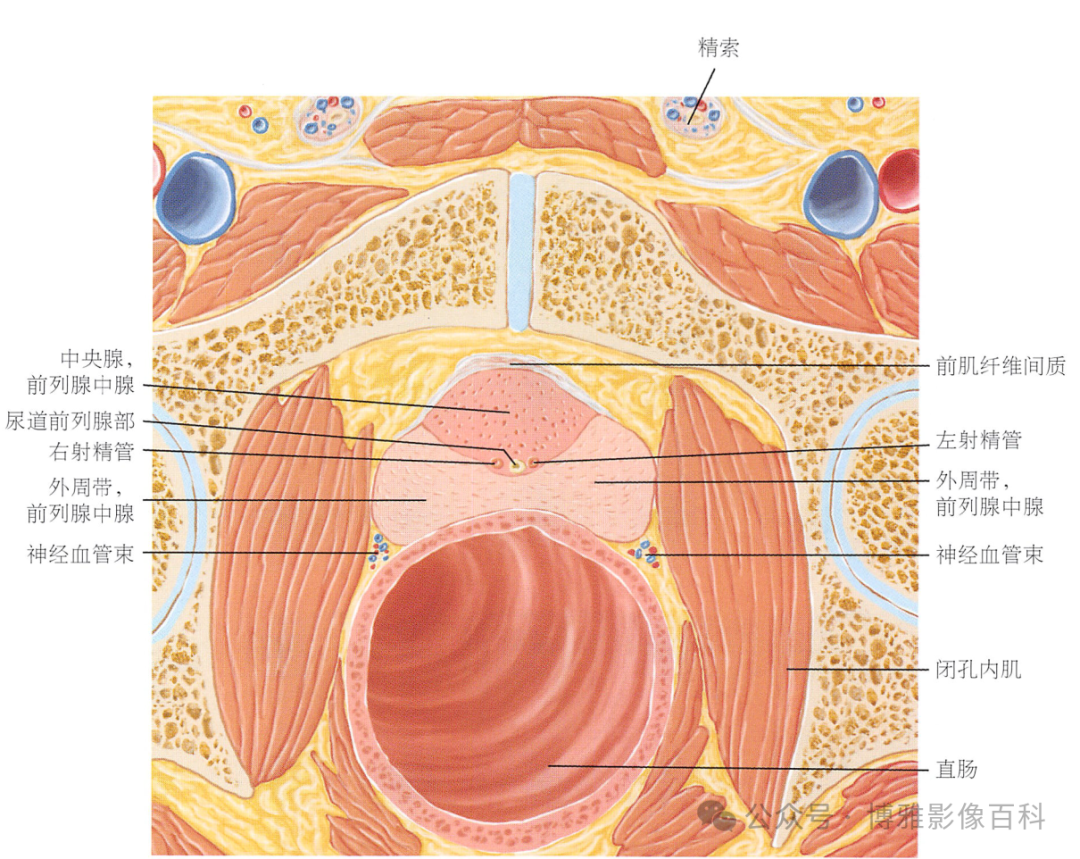

解剖学

前列腺分区解剖学

MR 解剖学